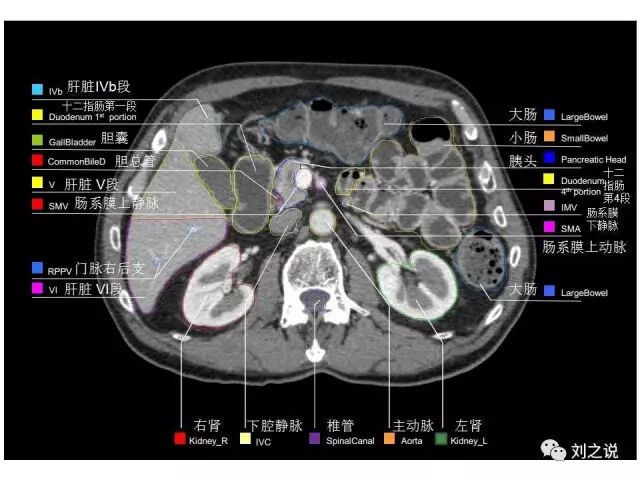

【解剖】高清实用 腹部CT断层

参考RTOG共识和3D-body解剖。